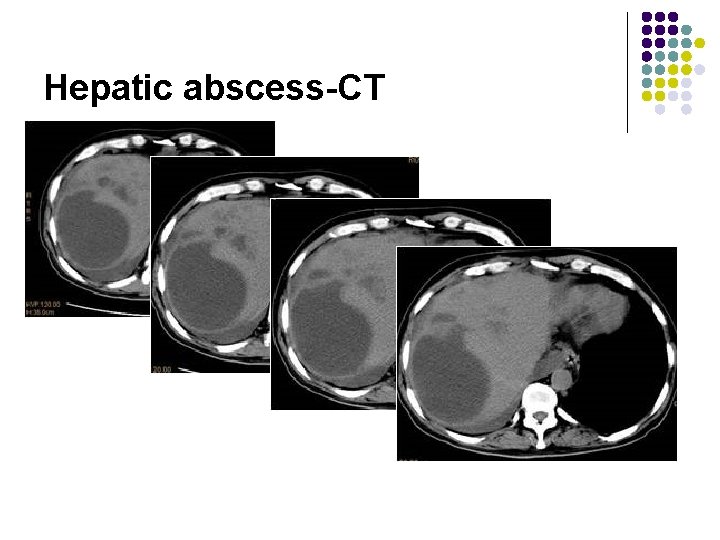

Hepatic abscess-CT